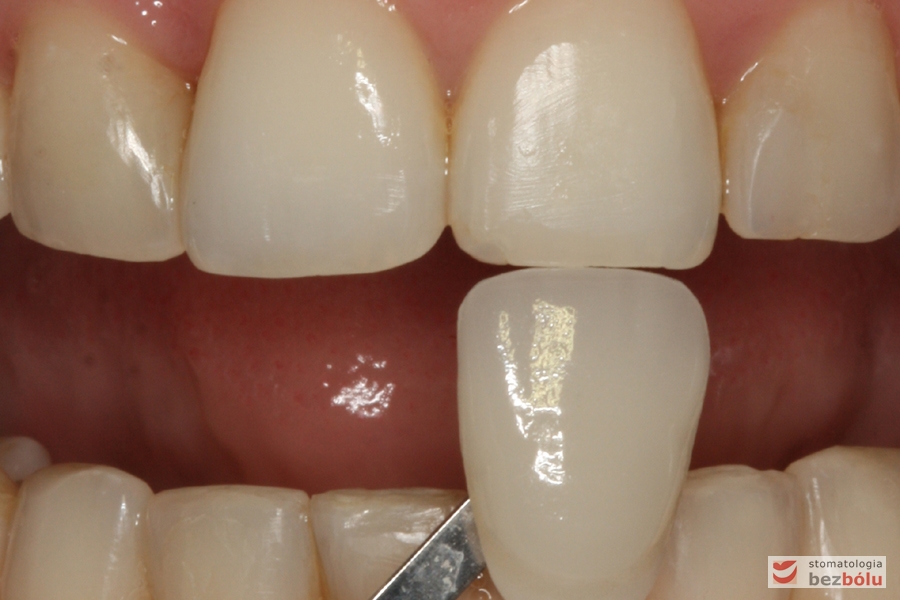

Ustalenie koloru względem siekaczy centralnych